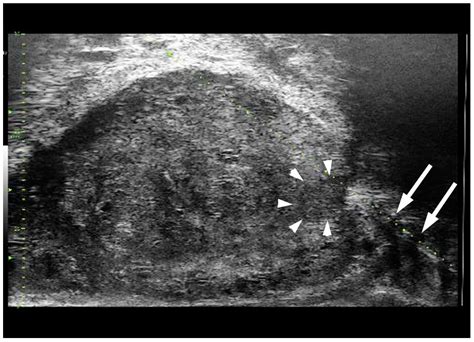

• Tumor Detection: Sonography can identify tumors and other masses that may indicate the presence of cancer. By examining the size, shape, and borders of these masses, healthcare providers can determine whether further investigation is necessary.

• Lymph Node Assessment: Cancer often spreads to the lymph nodes, and sonography can help assess their condition. Enlarged or abnormal lymph nodes may suggest the presence of metastatic cancer.

• Guided Biopsies: Sonography can guide needle biopsies, allowing doctors to extract tissue samples from suspicious areas for further analysis. This minimally invasive procedure helps confirm the presence of cancer and determine its type.

• Texture and Echo Pattern: The texture and echo pattern of the tissues are analyzed to determine if they are benign or malignant.

• Blood Flow: Doppler sonography may be used to assess blood flow within the tissues, which can provide additional information about the nature of the abnormality.

• Doppler Sonography: This technique uses Doppler effect to assess blood flow within tissues, helping to differentiate between benign and malignant masses.